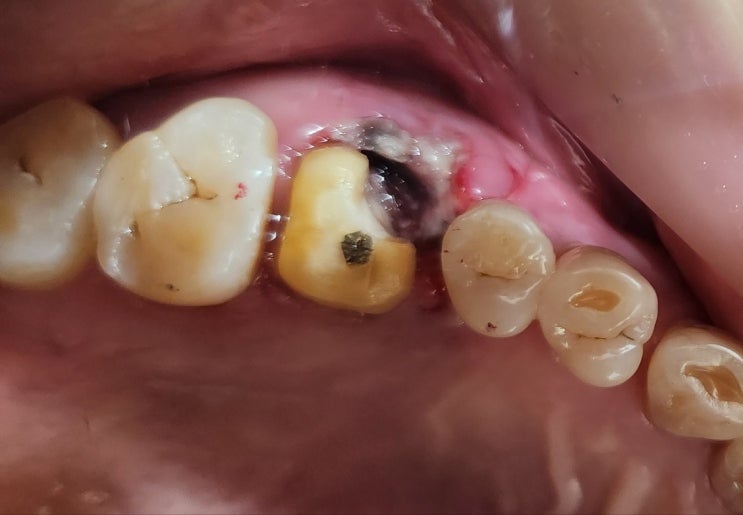

사랑니 자가치아이식 시술 12년 경과 모습 및 상악 완전매복 사랑니 수술발치 후 하악대구치에 자가치아이식

12년전 저에게 사랑니 자가치아이식 시술을 받고 한참을 내원 안하다가 왼쪽 아래 제1대구치의 발치진단을 ...

사랑니 자가치아이식 12년 후

임플란트 대신 사랑니 자가치아이식을 시술받은지 12년된 환자분이 오랜만에 내원하셨습니다. 저는 당연히 ...